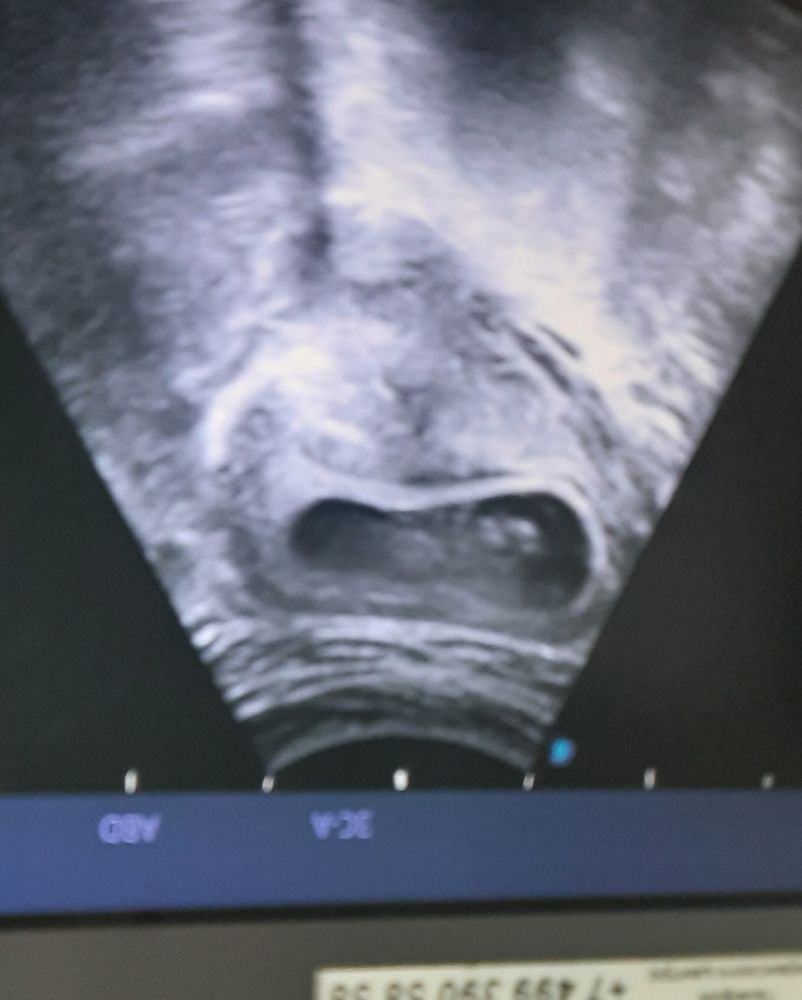

Узи в 11 недель

Головка справа, ручки вытянул вверх, как будто трогает руками потолок)))

Не очень качественный снимок, но головка справа , лежит на спинке ручки вверх)

Мне кажется, справа головка и ручки к верху

Какое непривычное УЗИ. Справа голову вижу)